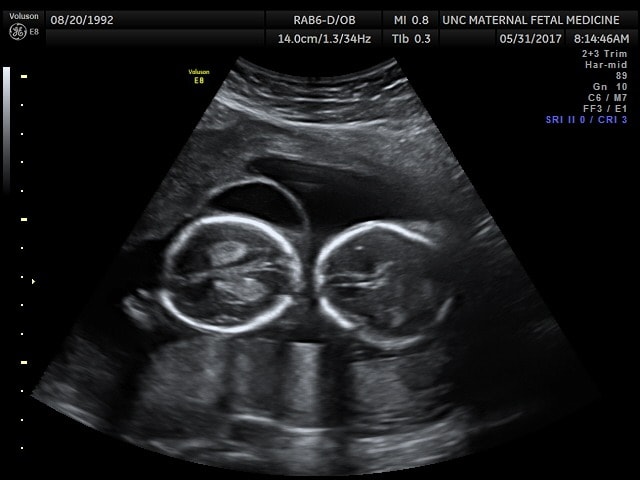

Ultrasound Photos at 18 Weeks Pregnant With Twins